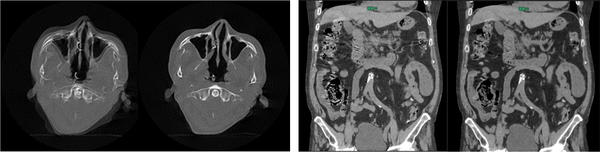

StillShotは収集したRaw Dataから被写体の動く方向と量を4次元的に算出する際に,体軸方向の連続性を広範囲に維持することでブレの少ない画像を提供する。胸部,心臓だけでなく,頭部や腹部においても,撮影中の被検者の動きによる画像のブレを補正して,アーチファクトの少ない画像を作成する。

Body StillShot2(各 左:処理前 右: 処理後)